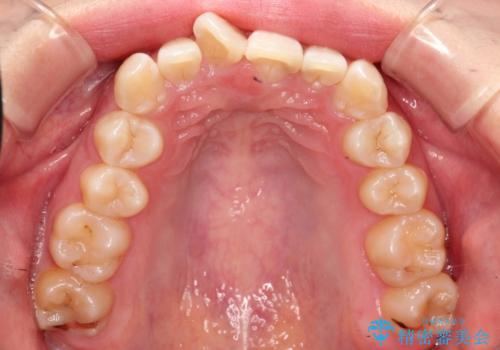

ハーフリンガル ワイヤー矯正による非抜歯・過蓋咬合の治療

- 非抜歯、大臼歯遠心移動による臼歯関係の是正・過蓋の改善をハーフリンガル・ワイヤー矯正にて計画した。

現在過蓋咬合の非抜歯治療はマウスピースで行うのが第1選択といっても過言ではありません。

しかし、諸々の理由でマウスピース矯正をおこなえない場合、本例のようにワイヤーを用いて治療することも可能ですが、そもそも装置が歯につかないため、非常に大変な労力を費やすことになります。